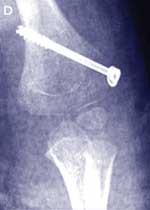

Case study — a 4-year-old girl with a painful left elbow after a fall

The parents of a 4-year-old girl bring their daughter to you after she has fallen about 1 metre from climbing equipment onto her outstretched arm. The girl is complaining of pain in her left elbow. She is unable to straighten her arm without pain and can only flex to 110°. The elbow looks swollen, mainly on the medial aspect. She has diffuse tenderness around the elbow and is unable to supinate or pronate her arm. There is no neurovascular compromise. Management

Lateral condyle fractures are inherently unstable and take a longer time to heal than supracondylar fractures. They should be managed by internal fixation in most cases. This case illustrates that it may be difficult to diagnose these fractures and that close follow-up is needed to prevent complications. |